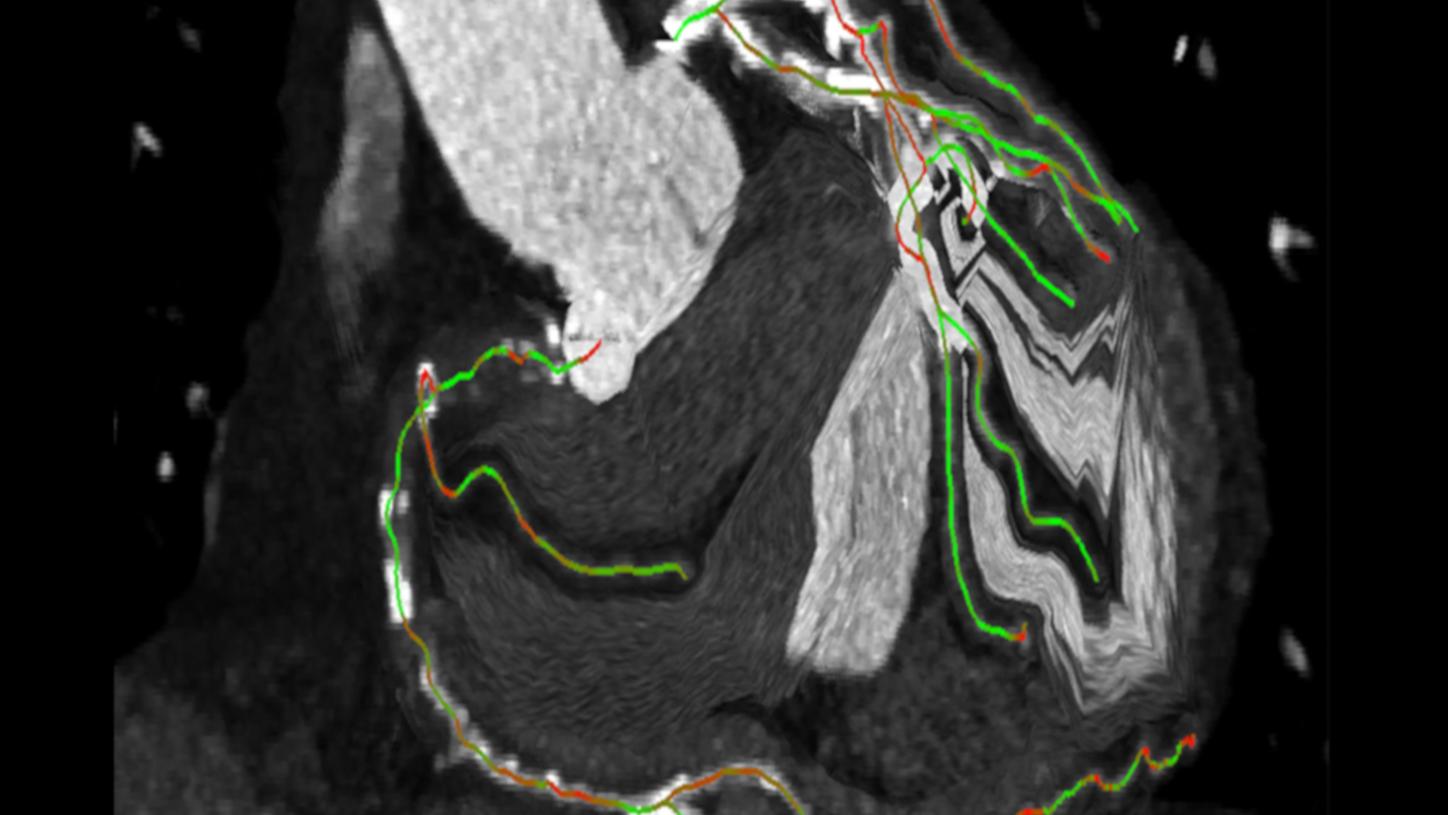

Options & Upgrades for your Magnetic Resonance Imaging system

Browse our clinical software applications and packages for Magnetic Resonance Imaging or request a trial license and discover the broadest coil portfolio.